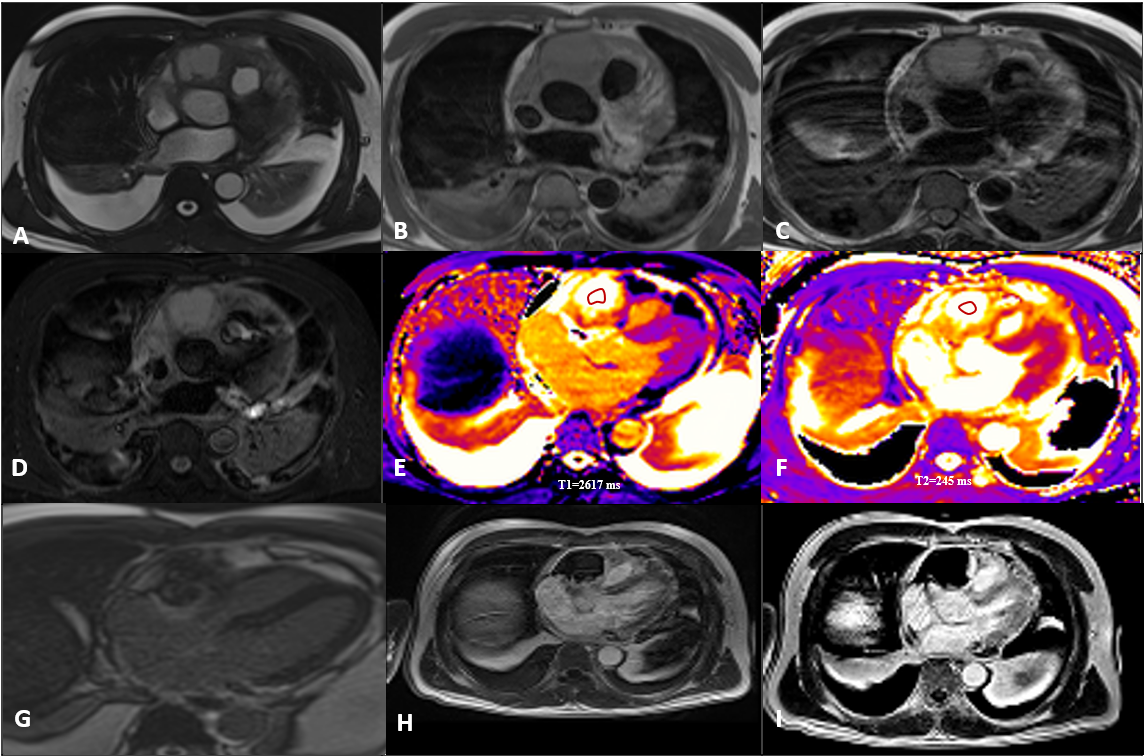

Figure 2. Tissue characterisation of the tumour. A. Cine SSFP (T2/T1 weighted image). B. T1-weighted sequence. C. T2-weighted sequence. D. STIR sequence. E. Native T1 map. F. T2 map. G. Early Gadolinium enhancement. H/I. Late Gadolinium enhancement (Magnetisation/PSIR).